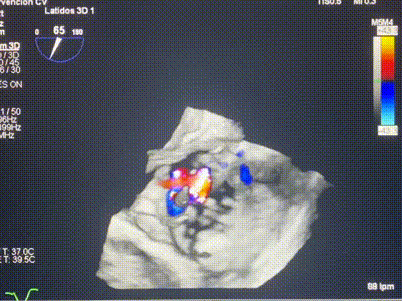

術(shù)中輸送器在超聲引導(dǎo)下調(diào)整位置

手術(shù)在全麻狀態(tài)下進行。術(shù)者采用經(jīng)右側(cè)頸靜脈入路的方式將輸送器送入患者心臟內(nèi),在TEE及DSA引導(dǎo)下調(diào)整輸送器頭端角度,使得輸送器與三尖瓣瓣環(huán)平面垂直。在輸送器進入右心室后釋放室間隔錨定裝置,而后釋放瓣葉夾持件(2個耳片結(jié)構(gòu))成垂直狀態(tài)。在TEE及DSA確定夾持件固定至三尖瓣葉根部且位于右室側(cè)后釋放人工瓣心房側(cè)盤片。隨后調(diào)整瓣膜同軸性以及室間隔錨定件位置(貼合室間隔),前推藏針管并固定,進而釋放室間隔錨定裝置,并再次確認瓣膜位置、穩(wěn)定性及同軸性,合攏輸送鞘后撤出輸送器,完成LuX-Valve Plus人工三尖瓣瓣膜的植入,僅殘余微量瓣周漏。且經(jīng)手術(shù)中心電生理團隊評估,病人的起搏器和ICD功能沒有受到影響。